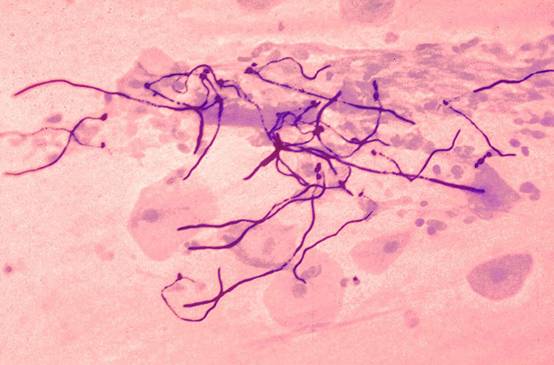

รูปที่ 3 ตกขาวแบบ “เชื้อรา” จะมีลักษณะเป็นก้อนแบบลิ่มนมในปากเด็ก

รูปที่ 4 เมื่อนำก้อนรามาย้อมแล้วส่องกล้องจุลทรรศน์จะพบเชื้อราเป็นสายพร้อมกับสปอร์ที่กำลังแบ่งตัว